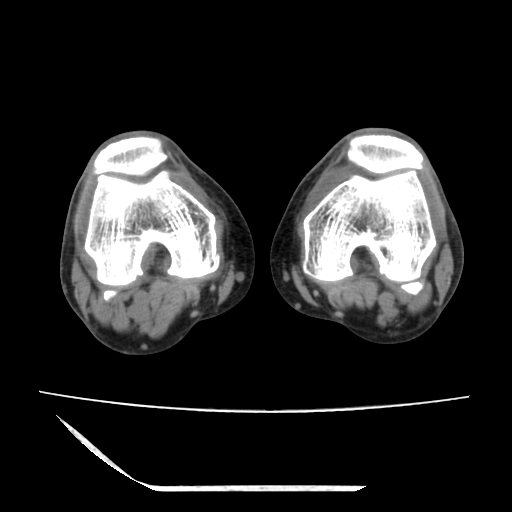

标题: CT13225:老年男性,左膝关节疼痛数月;请各位老师讨论。 [打印本页]

标题: CT13225:老年男性,左膝关节疼痛数月;请各位老师讨论。

骨质增生,骨性关节面硬化,关节积液,考虑退行性骨关节病

关节腔内少量积液,关节面退变。

双膝退变

骨质增生,骨性关节面硬化,关节间隙失常,关节积液,考虑退行性骨关节病.

骨质增生,骨性关节面硬化,关节积液,考虑退行性骨关节病。

这是由于两侧的肌肉不对称所致,加上扫描的平面也有些差异。请看示意图:

这个病例诊断:退行性骨关节炎